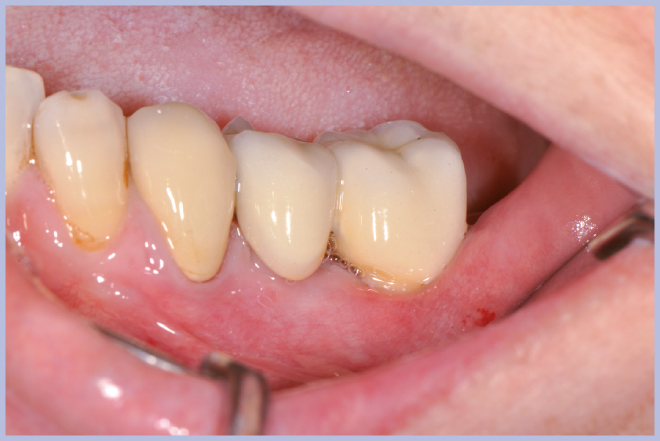

Dopo due settimane, a guarigione dei tessuti molli avvenuta, si iniziano le fasi protesiche per finalizzare il caso con posizionamento di due corone in metalloceramica (Figg. 37-40).

- Figg. 37-40 – Fasi protesiche e finalizzazione con posizionamento di due corone in metallo ceramica

- Fig. 38

- Fig. 39

- Fig. 40